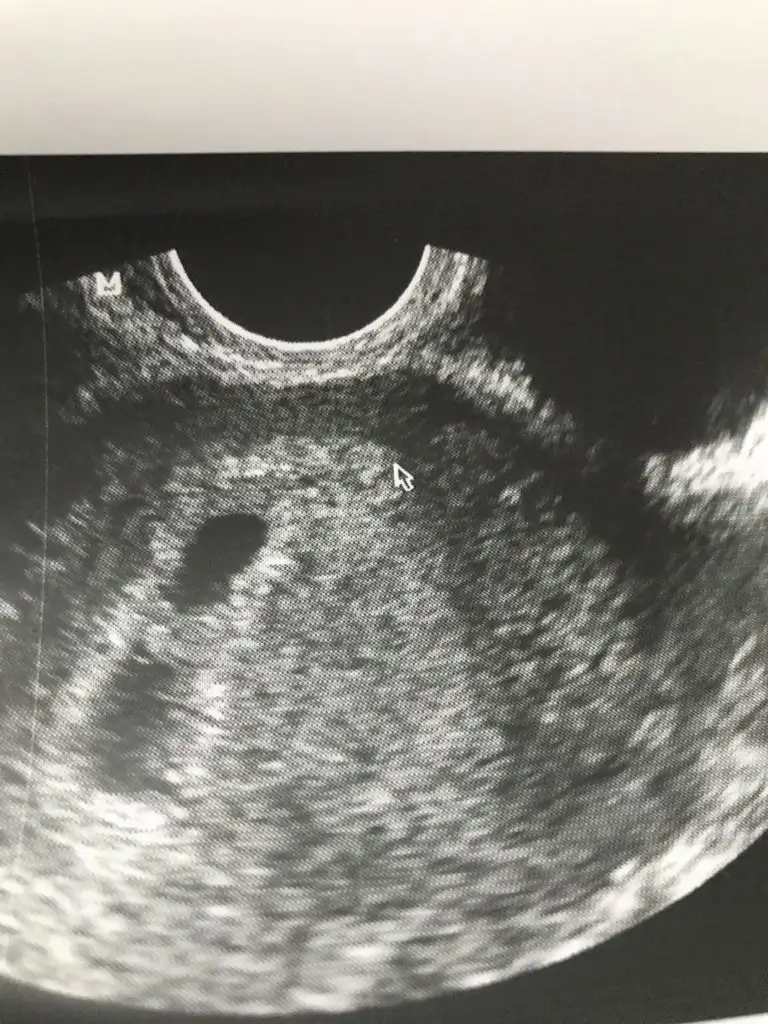

Canım bi bakar mısın ultrason fotoğrafımaKızlar bı arkadaş keseye göre tahmin yapıyor ve hep tutuyormuş iki oğlunu da bu şekilde cok yeniyken bile tahmin etmiş...ogullarinda kesesi hep uzunmuş muz gibi...yuvarlak ve yuvarlağa yakın olanlar hep kızdır diyor..ve bayağı emin konusuyor..benimki şişman bı fasulye gibi oo kesin kız görürsün dedi...sizlerin keselerinin şekli nasıldı ve cinsiyet neydi konusalimmi

burdaki sölenenlere göre kız gibi duruyor :))Kızlar tahmini olan var mı bildiğiniz fasulye gibi 6+4